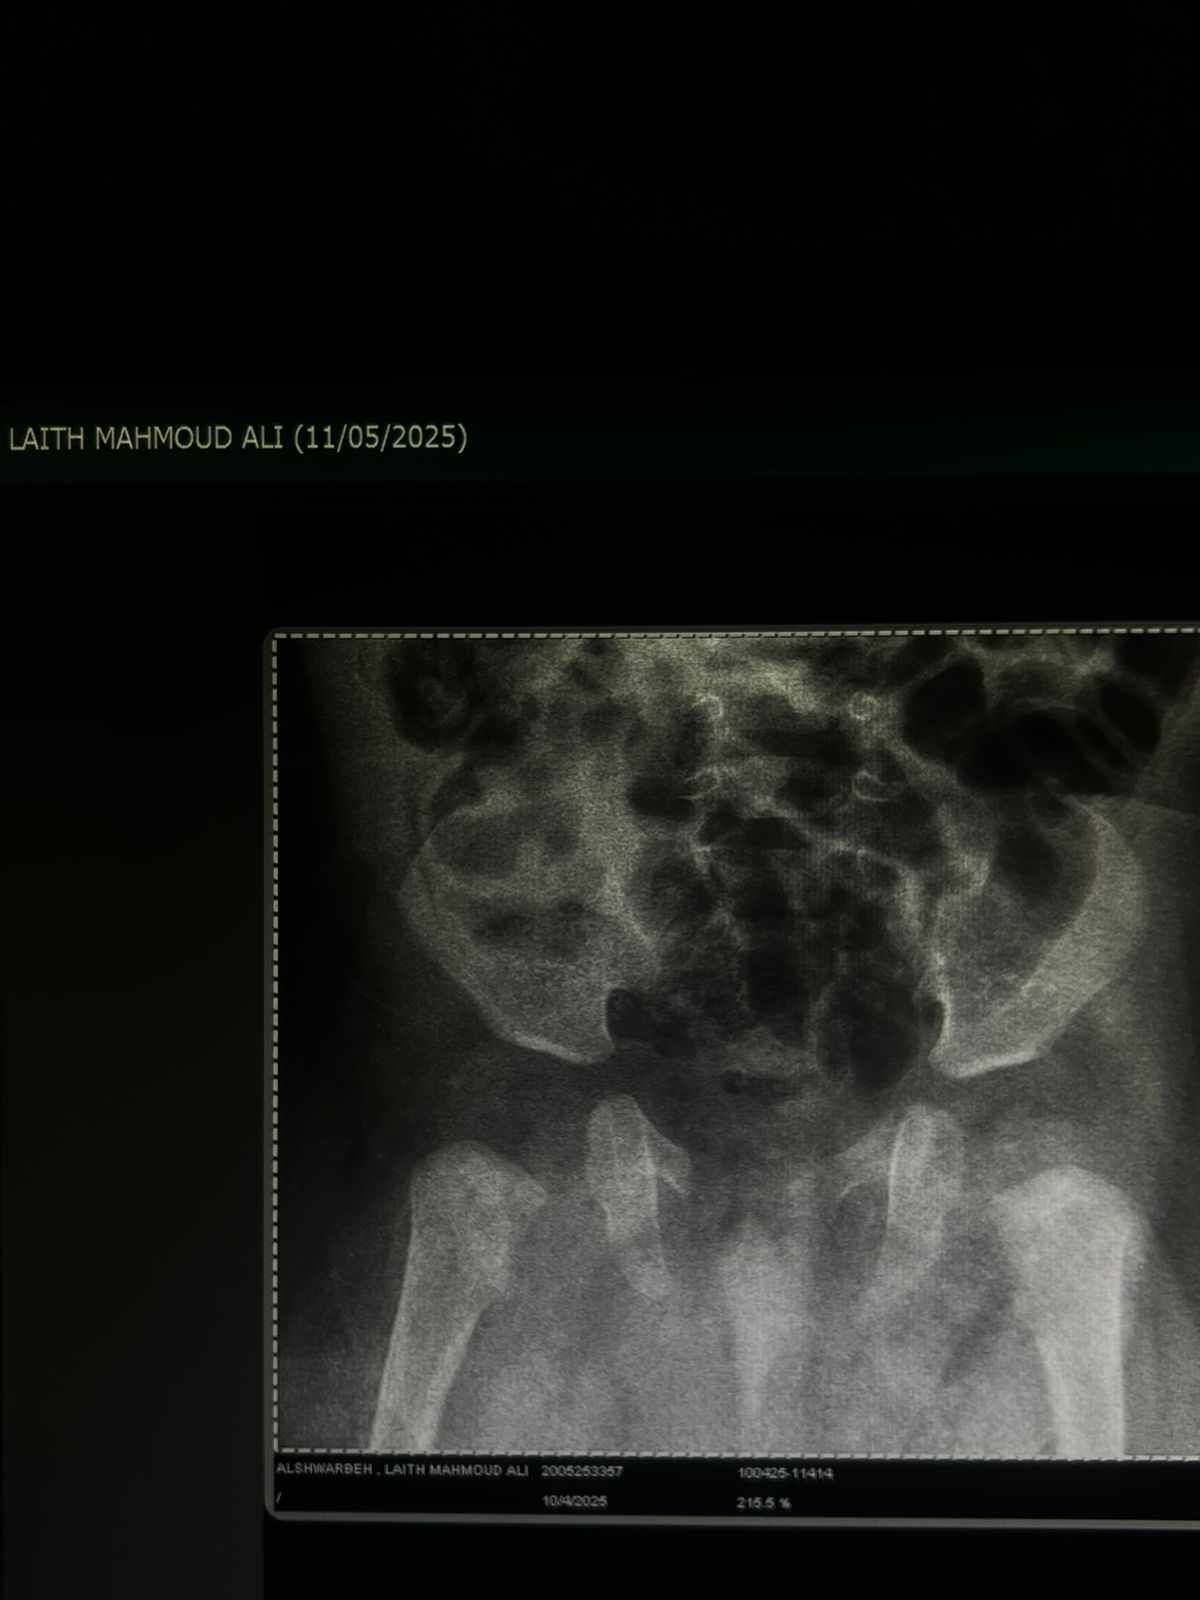

هل يوجد خلع ولادة او اي مشاكل بالصورة

شاهدت الصورة

وهناك تسطح خفيف في جوف المفصل الحقي الأيمن (من جهة التاريخ المكتوب على الصورة)

وقد يكون بداية خلع ورك او تحت خلع خفيف(درجة بسيطة من الخلع)

وكون الطفل توأم وهناك شك بالخلع فالافضل إجراء صورة بالسونار او امواج فوق صوتية للمفصلين